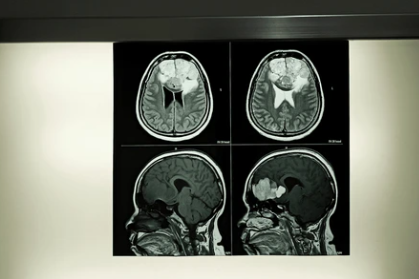

No. MRI does not cause cancer. Unlike CT scans or X-rays MRI uses magnetic fields and radio waves not ionising radiation. There is no radiation entering your body during an MRI scan. None. Zero. The fear around MRI and cancer is completely understandable but it has no scientific foundation and avoiding a scan your doctor needs because of this fear causes real harm.

- MRI Gets Grouped With CT and X-Ray in People’s Minds as Radiation Based Imaging: CT scans and X-rays use ionising radiation that can theoretically damage DNA with repeated exposure but MRI operates on completely different physics involving magnetic fields and radio waves that carry no such risk whatsoever.

Yes, multiple MRI scans carry no cumulative radiation risk because MRI uses magnetic fields and radio waves rather than the ionising radiation that creates dose related concerns with CT scanning.

Yes, MRI provides superior soft tissue contrast making it more accurate than CT for brain, spinal cord, pelvic organs and soft tissue tumours while CT remains better for lung and bony detail.